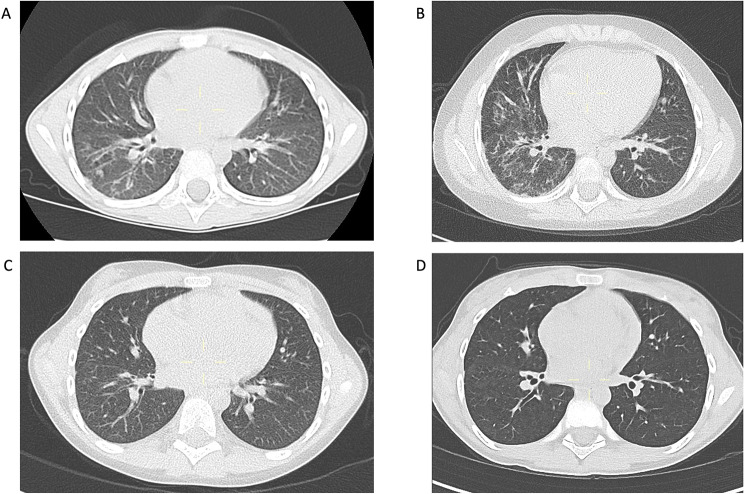

Successful treatment of an anti-MDA5 antibody-positive Juvenile Dermatomyositis patient with refractory interstitial lung disease using tofacitinib.